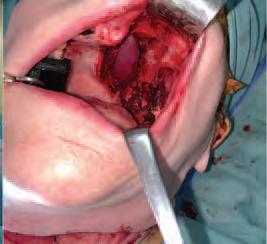

The zygomatic implant perforated (ZIP) flap for rehabilitation of patients with midfacial oncology defects: a report of three cases B. Martin, E. Cotter, C. Bowe, J.E. O’Connell

Issuu converts static files into: digital portfolios, online yearbooks, online catalogs, digital photo albums and more. Sign up and create your flipbook.